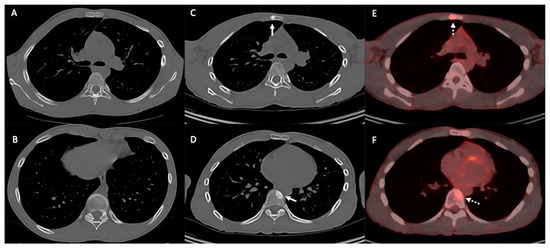

2.2. Vascular Metastasis

5. Cardiac and Major Thoracic Vessels

6. Chest Wall